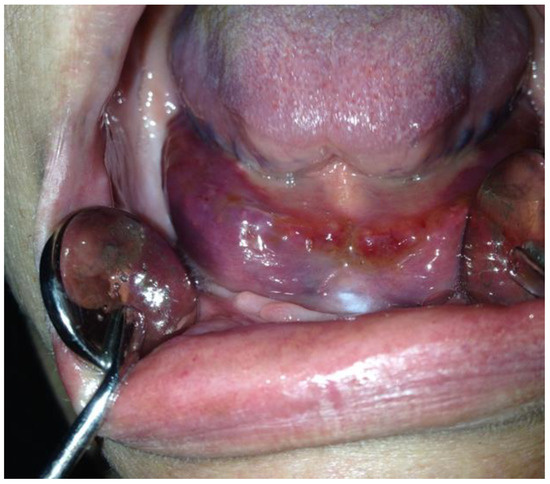

Oral Manifestations of Vitamin C Deficiency